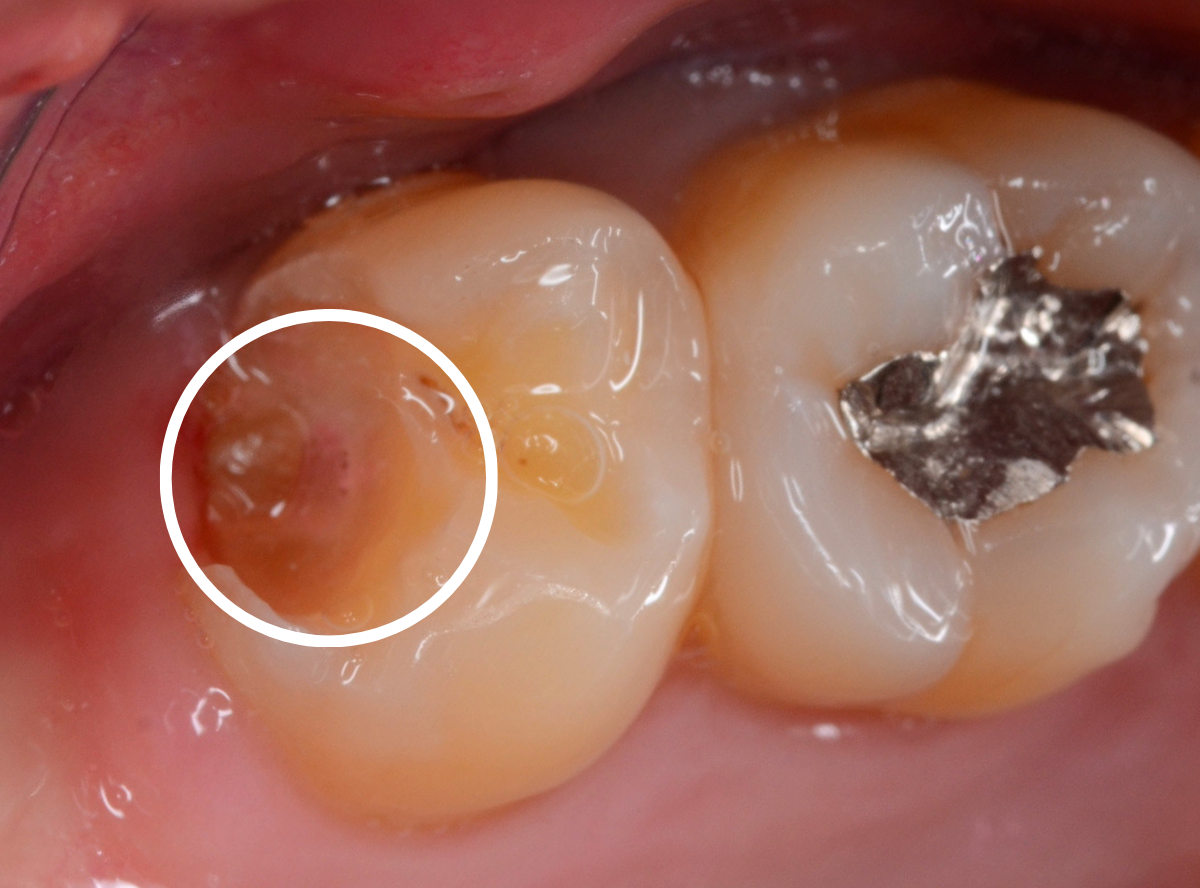

Case.6 上の奥歯の、見えづらいところで虫歯が進行!

こちらも上の一番奥の歯が深い虫歯になってしまった方です。

歯の頬側から奥側にかけて大きな虫歯になっているのがわかります。

カメラではうまく撮れましたが、実際は歯ブラシが届きづらく、虫歯になりやすいところです。

頬側の写真です。

ボコッと虫歯で穴が空いている状況ですが、本人には自覚症状がありません。

自覚症状がないから問題ないわけではない、というのがわかりますね。

治療を開始すると、大きな虫歯が出てきました。

虫歯を全て除去したところです。

赤い小さな点が見えているのは、歯の神経が少し見えてしまっている状態です。

運が悪ければ、神経を取る治療が必要になるかもしれません。

神経を保護するお薬をつめ、セメントで蓋をして、しばらく経過観察をします。

あとは痛みが出ないように祈ります。。。